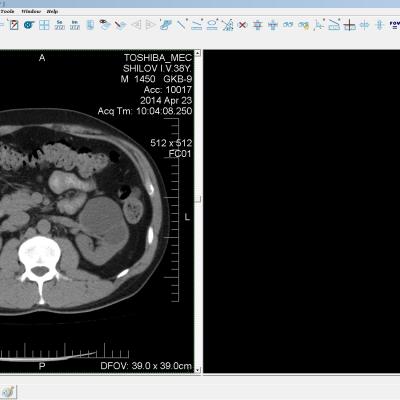

Здравствуйте. У меня киста левой почки. Из заключения: левая почка увеличена, деформирована за счёт наличия в среднем сегменте округлого жидкостного +6, +15 HU образования 66х53 мм, деформирует, поддавливает чаше-лоханочную систему. Сосудистые ножки структурные. В урологии мне сперва предложили лапароскопию, когда я лёг на операцию - изменили на полостную в связи со сложностью. Потом сказали что шансов вырезать кисту без почки практически нет. Даже если кисту удалить чудесным способом, то почка всё равно сложится и не будет работать. В итоге операцию отменили. Скажите, пожалуйста, есть ли современный метод удалить кисту и сохранить почку в моём случае? Томография почки в приложениях. Заранее благодарю.

Эту кисту можно просто пропунктировать, аспирировать и склерозировать - под местной анестезией. Ничего сверхестетственного не определяется по данным КТ. Можете написать мне на почту. aristova-tatyana@mail.ru